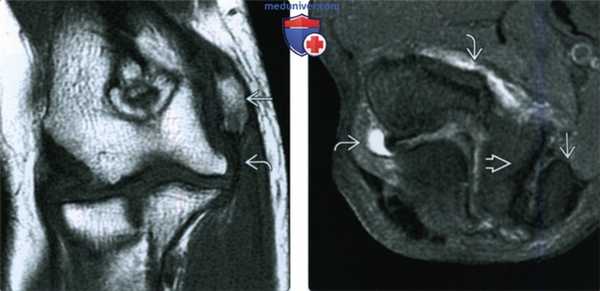

4. МРТ при чрезмыщелковом (надмыщелковом) переломе локтевого сустава:

• Линия перелома пересекает медиальный и латеральные мыщелки

• Без перехода на суставную поверхность дистального эпиметафиза плечевой кости

• Редко с захватом дистальной зоны роста плечевой кости

о Высокий сигнал на Т2ВИ FS в зоне роста

о Расширение зоны роста

• Внутрикапсулярная локализация перелома

• Суставной выпот/гемартроз